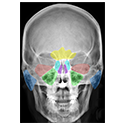

NEUROANATOMY